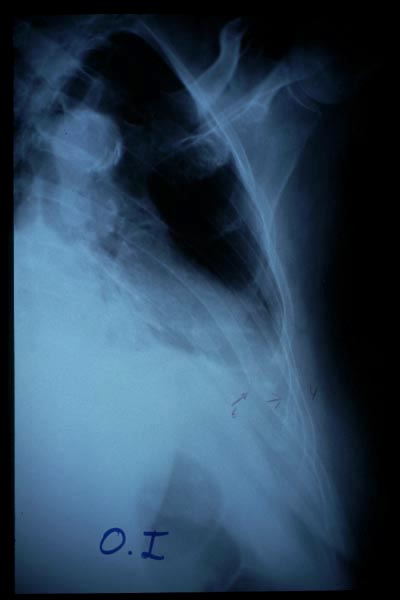

MO Fractura de omóplato y de costillas 2 a 8 derechas. Accidente de tráfico con moto en paciente centenaria. 1

MO Fractura de omóplato y de costillas 2 a 8 derechas. Accidente de tráfico con moto en paciente centenaria.2